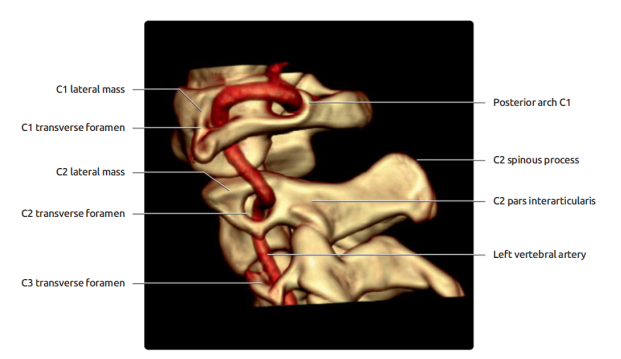

Vertebral arteries

• V1 – origin (subclavan) to the point of entrance into

cervical tranverse process (usually C6)

• V2 – passes through tranverse processes to C2

• V3 – Exit at C2, laterally and posteriorly to pass

through transverse process of C1, the posteriomedial in a groove on the upper

surface of posterior arch of C1.

• V4 – Pierces dura and extends through foramen magnum –

up to basilar artery